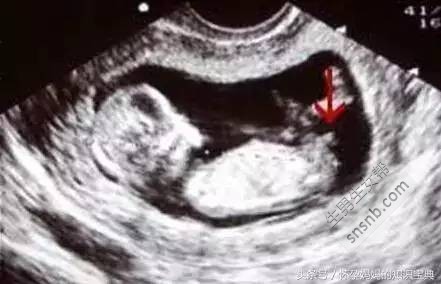

三、国外新奇小肿块原理

个别有经验的妈妈还有另一种看图方式:十一至十三周,所有的胎儿都会在双腿之间长出一个小肿块,而这个肿块的角度则会显示出它是个男孩还是女孩。据说如果小肿块翘起来30度以上就是男孩,但如果小角度就是女孩。请看下面的例子。

小肿块没有指向三十度以上 - 事实上它几乎是水平的!

小肿块以一个陡峭的角度向上指,显示这个胎儿是个男孩。

如果你可以得到一张侧面图,那么它应该会给你提供一个很好的观察小肿块的角度。